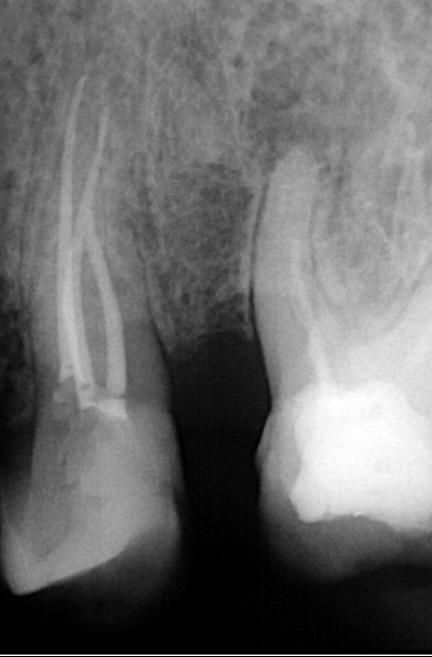

Premolar presenting with an aberrant molar-like multi-canal morphology and extensive coronal caries, requiring meticulous access preparation and maximum structural preservation.

- Safely negotiating and managing a highly intricate, molar-like canal network within the inherently more restricted anatomical dimensions of a premolar root.

Adequate access was essential—not only to locate and negotiate the canal system but also to do so while conserving as much tooth structure as possible. Once the decay was fully removed and access achieved, shaping was carried out using the DENCO Chameleon Dual Shaper. This instrument allowed for conservative and controlled preparation, effectively preserving the original canal anatomy and minimizing excessive dentin removal. Respecting the internal morphology throughout the procedure was key to maintaining canal integrity.

Obturation was completed with gutta-percha and CeraSeal bioceramic sealer, resulting in a stable, well-adapted three-dimensional seal.

Successful negotiation of the complex canal system was achieved following complete caries removal. Shaping with the DENCO Chameleon Dual Shaper enabled conservative, controlled preparation that fully respected the internal morphology and minimized pericervical dentin loss. A stable, three-dimensional seal was accomplished using gutta-percha and CeraSeal bioceramic sealer after a rigorous chemical disinfection protocol.